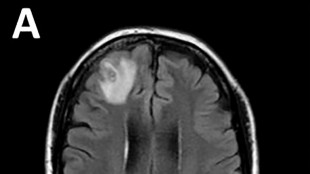

C'est une première mondiale porteuse d'espoir pour les personnes ayant perdu l'usage d'un oeil: des chirurgiens américains ont annoncé jeudi avoir réalisé la première greffe d'un oeil complet sur un patient, qui n'a toutefois pas recouvré la vue -- en tout cas pour le moment.